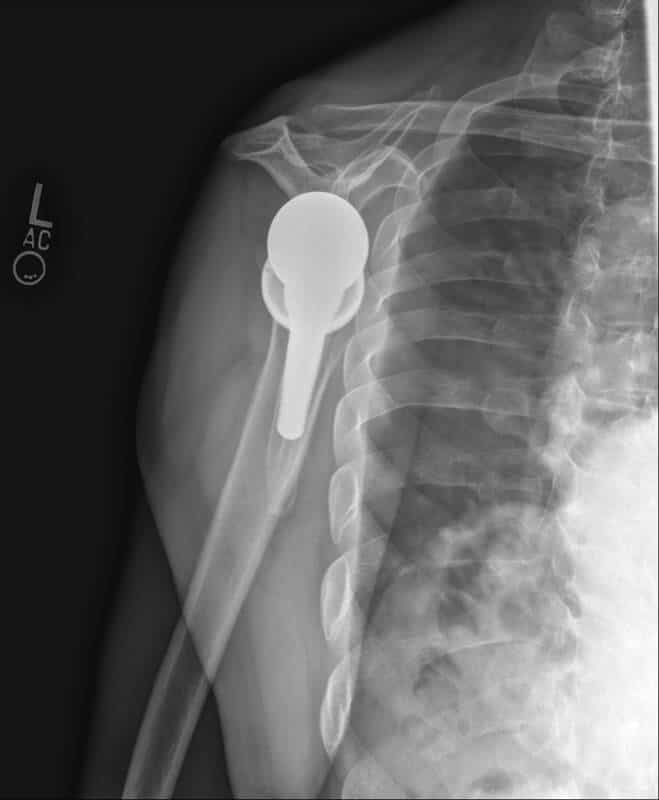

Stryker/Wright/Tornier, Ascend Flex